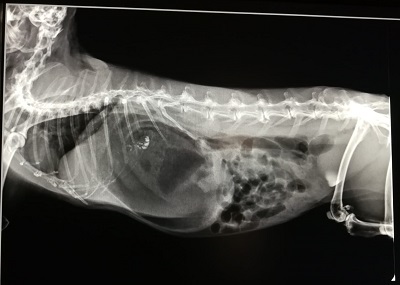

Pils is een konijn van 8 jaar dat plotseling stopte met eten. Het viel ook op dat ze een dikke buik had gekregen in korte tijd. Aangezien Pils samen zit met een ander konijn, wist de eigenaresse ook niet of Pils nog ontlasting had geproduceerd. Konijnen kunnen niet lang zonder voeding (2 dagen is de regel) voordat de darmen stilvallen en ze daardoor vaak snel overlijden. Pils' eigenaar was hier gelukkig van op de hoogte en is meteen op zondag in de dienst naar ons toegekomen. Pils haar temperatuur was veel te laag en haar buik erg opgezet. Er werd besloten om een foto te nemen. Hierop bleek dat de maag gigantisch was vergroot; dit kan ontstaan als de maagwand te weinig beweegt (ileus). Gas gaat zich ophopen in de maag (of darmen) wat zeer pijnlijke krampen geeft. Hierdoor stopt het konijn met eten wat de situatie erger maakt.

Meteen is dwangvoeding opgestart, evenals pijnstilling en verschillende middelen om de darmen weer op gang te krijgen. Gelukkig kwam de eerste keutel 's nachts weer tevoorschijn! Er is ook massage van de buik toegepast. En Pils werd zo veel mogelijk gestimuleerd om te bewegen. Dit was de eerste uren erg onwennig, maar later kwam ze weer op gang. Inmiddels eet Pils als nooit te voren, ze heeft behoorlijk wat in te halen! Konijnen zijn gevoelige dieren maar laten slecht pijn zien. Gelukkig waren we er dit keer op tijd bij, mede door de scherpte van de eigenaar.